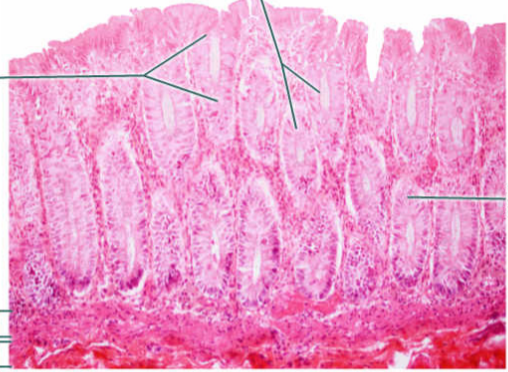

A

Mucosa: simple columnar epithelium with microvilli

B

Submucosa

C

muscularis mucosa

Area

Small intestine

E

simple columnar epithelium with goblet cells and microvilli

F

Villi

G

Lamina propria

Area

Large intestine

Large circles

Goblet cells

Epithelium

Simple columnar